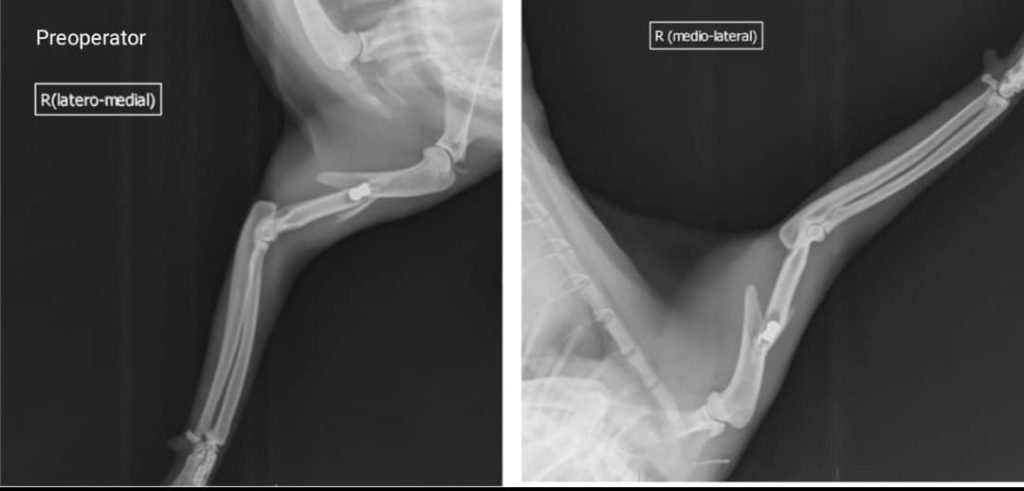

Fractură de humerus produsă prin împușcare, un tip de traumatism sever care necesită o abordare chirurgicală complexă și un protocol atent de monitorizare. Radiografiile realizate înainte de operație au evidențiat traiectul proiectilului și zonele cu pierdere osoasă, permițând planificarea exactă a intervenției.

Stabilizarea a fost realizată cu implanturi ortopedice dedicate, iar imaginile postoperatorii confirmă obținerea unei alinieri corecte și a unei fixări stabile. Evoluția pacientului a fost urmărită radiologic de-a lungul procesului de vindecare, observându-se formarea progresivă a calusului și consolidarea completă a osului.

După confirmarea vindecării osoase, implanturile au fost extrase pentru a elimina orice risc de complicații pe termen lung.

Pacientul s-a recuperat integral, fără sechele funcționale, recăpătându-și mobilitatea și confortul. Acest caz subliniază importanța unei intervenții rapide, a unui protocol chirurgical modern și a unei monitorizări riguroase în traumatologia severă.